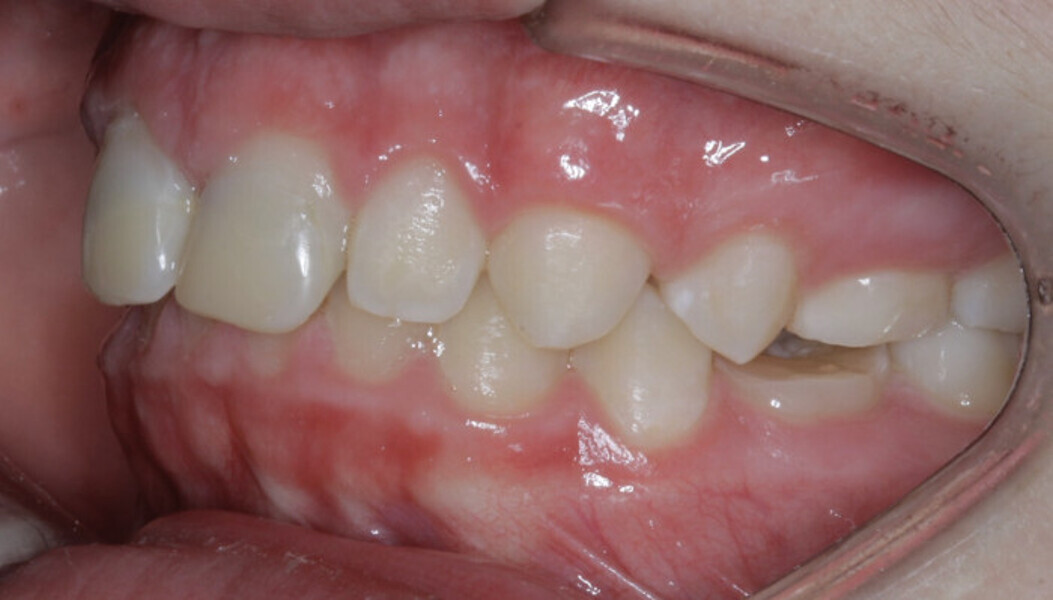

New Age orthodontics and orthopaedics with temporary anchorage devices